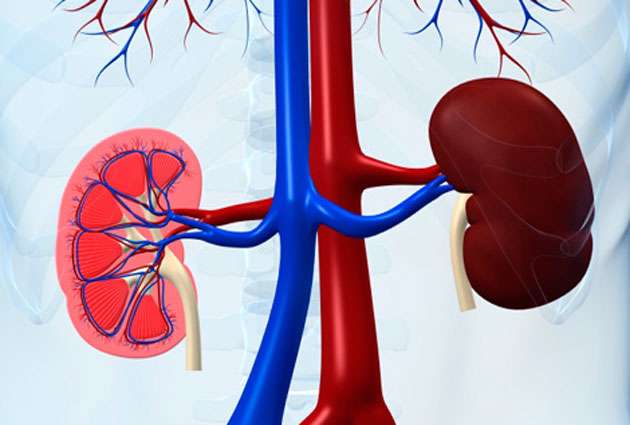

किडनी को शरीर का एक महत्वपूर्ण अंग माना जाता है। यह शरीर के लिए फिल्टरनेशन सिस्टम की तरह काम करता है। इसकी मदद से अपशिष्ट पदार्थ बाहर निकलते हैं। हालंकि, जब किडनी सही तरह से काम नहीं करती है तो इससे ब्लड को सही तरह से फिल्टर करना काफी मुश्किल हो जाता है। ऐसे में व्यक्ति को अन्य भी कई तरह की समस्याओं का सामना करना पड़ता है।